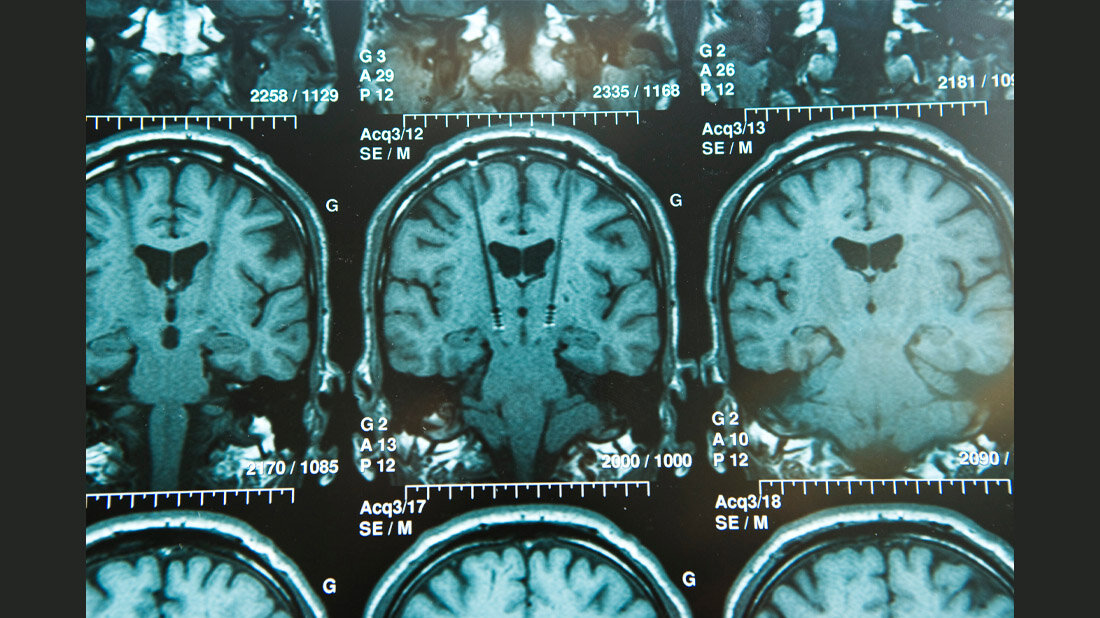

Mit weltweit mehr als 100 Millionen Untersuchungen pro Jahr ist die Magnetresonanztomografie (MRT) das zweitwichtigste medizinische Bildgebungsverfahren nach dem Röntgen. Ein neuer Ansatz könnte Millionen von Patientinnen und Patienten mit Implantaten helfen und die Arbeit des Radiologiepersonals erheblich vereinfachen. Denn wer ein Implantat trägt, muss oftmals auf diese potenziell lebensrettende Diagnosemöglichkeit verzichten oder eine geringere Bildqualität in Kauf nehmen. Insbesondere aktive Implantate wie Herzschrittmacher und Neurostimulatoren können in Kombination mit einer MR-Untersuchung bei unvorsichtiger Anwendung zu gefährlichen Erwärmungen im Körper führen. In der Physikalisch-Technischen Bundesanstalt (PTB) wurde nun demonstriert, wie mit einer drahtlosen Kommunikation zwischen Implantat und Magnetresonanztomograf dieses Problem gelöst werden kann.

Metallische Implantate im Körper stellen bei der Magnetresonanztomografie (MRT) ein Sicherheitsrisiko dar, da die Wechselwirkung des leitfähigen Implantats mit den starken elektromagnetischen Feldern des Tomografen zu einer gefährlichen Gewebeerwärmung führen kann. Das Personal muss im Einzelfall aufwendig und in eigener Verantwortung abwägen, ob ein MRT für die Gesundheit der Patientinnen oder Patienten vertretbar ist oder wie hoch die Strahlungsleistung ohne Gesundheitsschäden sein darf. „Wir wollen, dass ein ‚smartes‘ Implantat direkt mit dem MR-Scanner kommuniziert, der dann seinerseits die elektromagnetische Welle an das Implantat anpasst“, erklärt Dr. Lukas Winter, Wissenschaftler in der PTB. „So vermeiden wir eine Überhitzung und sorgen gleichzeitig für die bestmögliche Bildqualität. Für das Krankenhauspersonal wäre die Arbeitserleichterung enorm.“ Voraussetzung für die weitere Verbreitung dieser innovativen Technologie ist eine enge Zusammenarbeit von Implantat- und MRT-Herstellerfirmen – unterstützt von geeigneten Normen und Standards.